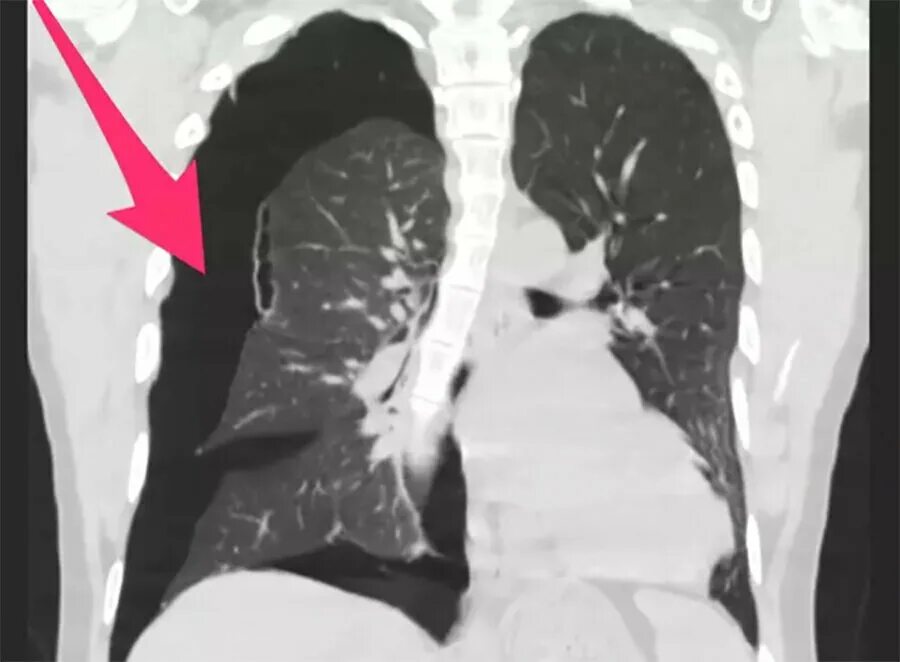

Флюорография видно ли курящего электронную сигарету